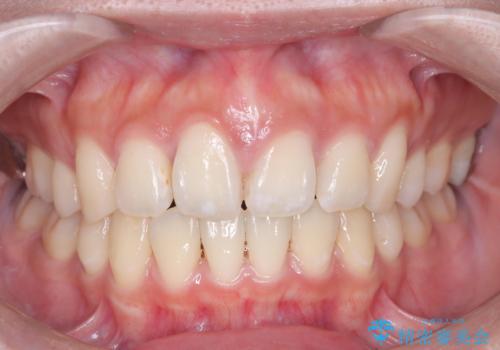

前歯の突出を防ぎながらガタつきを解消。上下左右4番抜歯による審美ワイヤー矯正